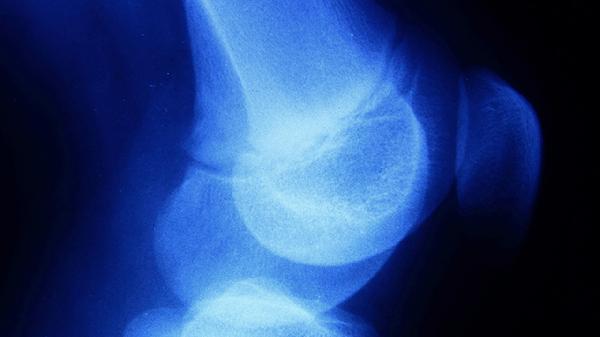

通过伊利扎罗夫外固定架进行胫骨或股骨截骨延长,每年可增长5-8厘米。需承受6-12个月康复期,存在感染、骨不连等风险。仅建议严重矮小症患者选择,需在骨科专科医院完成评估。